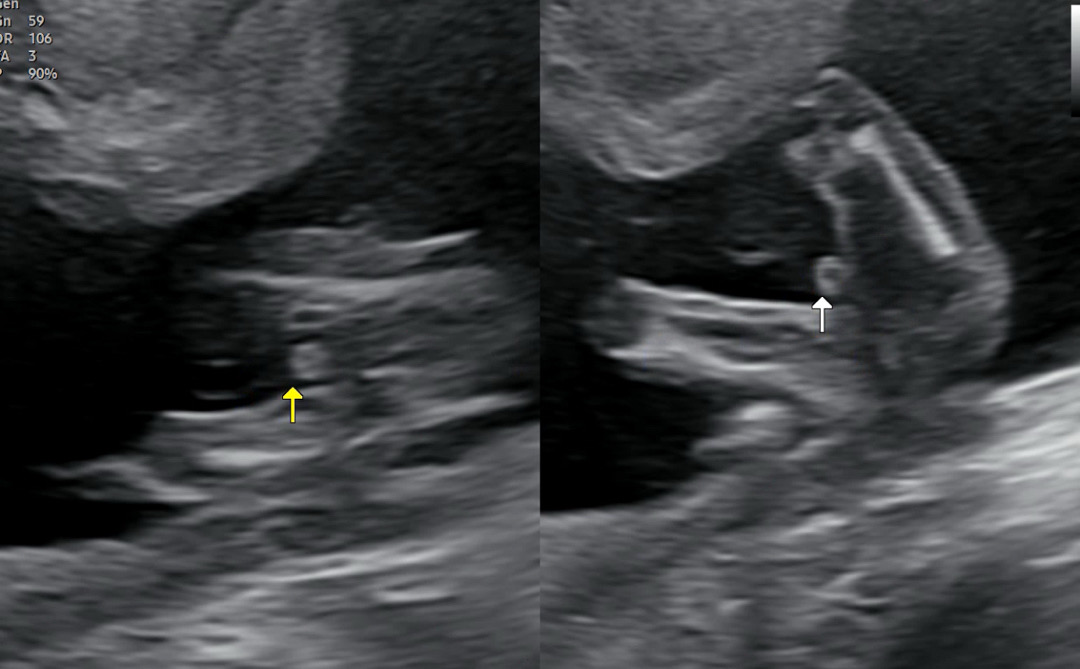

16주 1일차 성별 촘파,,!!

확정지어 이야긴 안해주시고 뭐가 보이긴하네요~ 하면서 콕 찝어주시며 4주뒤 정밀초음파로 다시보자하셨는데 아들일거같다고는 하시네요,,, 지인들은 아직 확정은 아니니 좀더 기다려보자 하는데 그래도 첫째가 딸이길 바랫다보니 쪼꼼 아쉽네여,,, 반전은 ... 없겠죠...?🥹